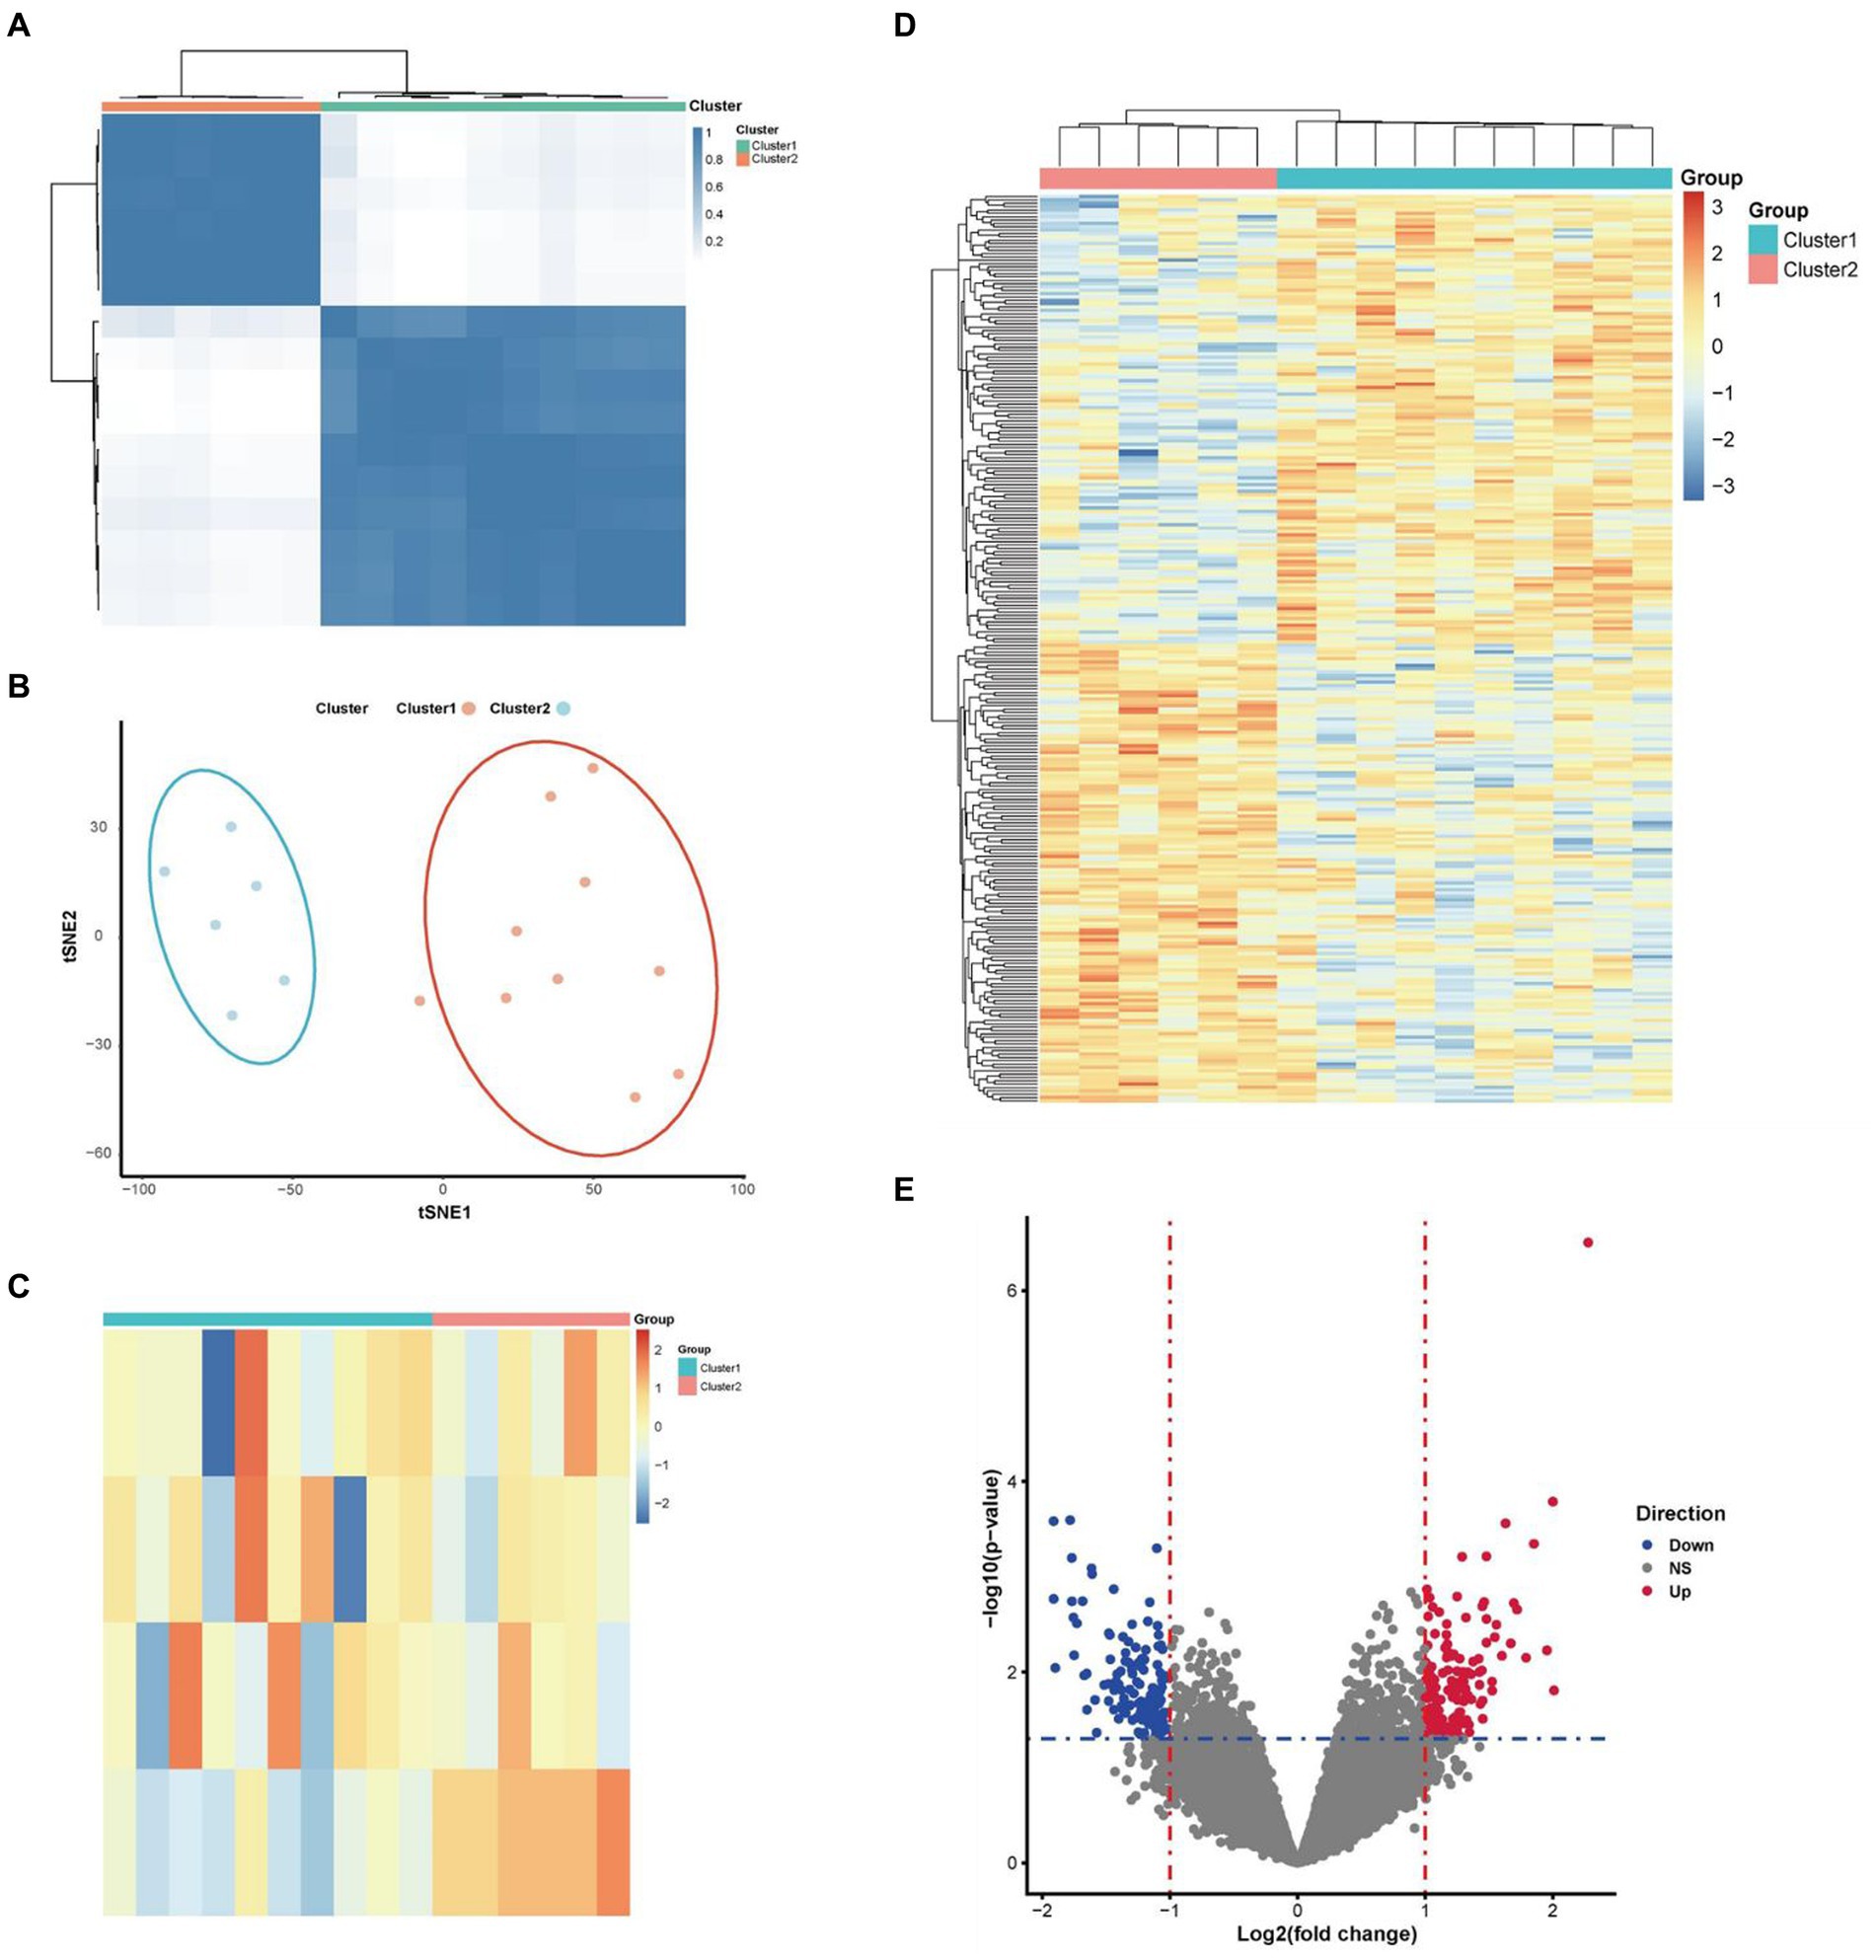

Frontiers in Parkinson Disease 2015年8月号(Vol.8 No.3。Optimal DaTQUANT Thresholds for Diagnostic Accuracy of。Frontiers | Identification of necroptosis-related genes in。